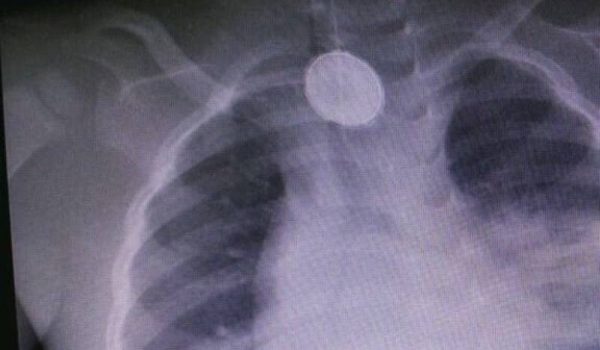

إستطاع فريق طبي سعودي إنقاذ حياة طفل عمره 3 سنوات، بعد إكتشاف قيامه بـ إبتلاع بطارية مستديرة قبل أكثر من شهر؛ وكان الطفل يعاني من مشاكل صحية.

ووصل الطفل الي مستشفى الولادة والأطفال بمكة المكرمة يعاني من صعوبة في التنفس، وارتفاع درجة الحرارة، وبإجراء الفحوصات والأشعة المطلوبة وتم اكتشاف بطارية أسفل الرقبة.

وقال الأطباء أن البطارية الكهربائية وجدت ملتصقة بجدار المريء، والقصبة الهوائية للطفل.